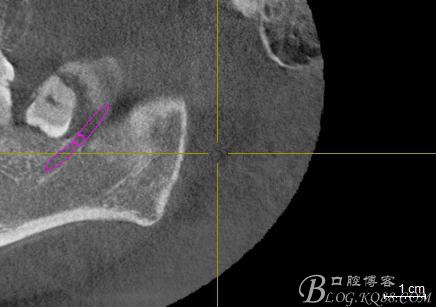

口內(nèi):38未萌出。37遠中牙周袋10mm,CT:38牙冠倒置。牙齦紅腫,捫診可有少量血性滲出,無波動感。印象診斷:38冠周炎。處理:1.抗炎治療,改善張口度。2.炎癥消退后,拔除38.

一、術(shù)前CBCT影像資料